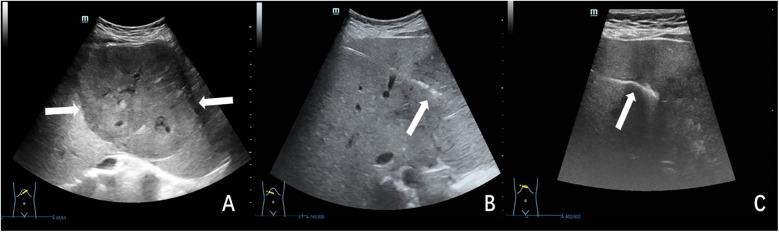

超声引导同轴针穿刺活检联合明胶海绵封堵在小儿肝脏活检中的应用

Application of ultrasound-guided coaxial needle biopsy combined with gelatin sponge plugging in pediatric liver biopsy.

The aim of this study was to assess the performance of utilizing the coaxial technique in conjunction with gelatin sponge slurry plugging for ultrasound-guided liver biopsy in children.

METHODS

We conducted a retrospective study of children undergoing ultrasound-guided coaxial liver biopsy at our institution between March 2020 and March 2025. Participants were stratified into two intervention groups: those receiving gelatin sponge tract embolization vs. batroxobin administered through needle tract. Through comprehensive electronic medical record review, we systematically extracted and compared the following outcome measures: (a) overall complication rates, (b) hemorrhage rates.

RESULTS

This study included 48 children, with 30 allocated to the gelatin sponge group and 18 to the batroxobin group. The gelatin sponge group demonstrated 9 complications (30.0%, 9/30), consisting of 5 pain events and 4 febrile episodes, while the batroxobin group experienced 6 complications (33.3%, 6/18), including 2 hemorrhage cases, 3 pain events, and 1 febrile episode. The overall complication rates showed no statistically significant difference between groups (30.0% vs. 33.3%,  = 0.809). However, a significant divergence was observed in hemorrhage incidence, with the gelatin sponge group demonstrating superior safety (0% vs. 11.1%,  = 0.044).

CONCLUSION

Compared to batroxobin tract injection, coaxial technique in conjunction with gelatin sponge slurry plugging significantly reduced hemorrhagic complications in liver biopsies for children, demonstrating superior safety. The finding supported its adoption as the preferred hemostatic method in children undergoing percutaneous liver biopsy.